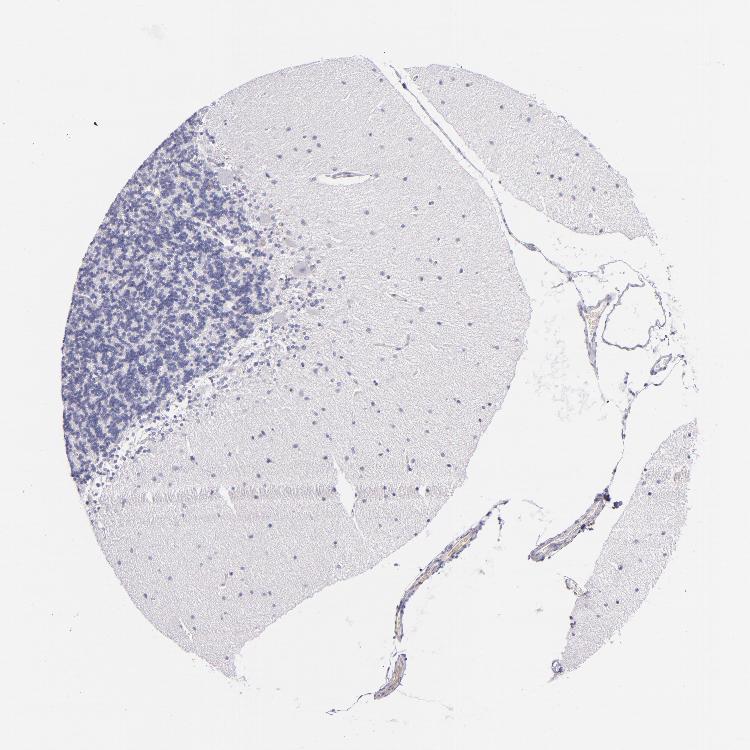

Antibody staining in the annotated cell types in the current human tissue is reported as not detected, low, medium, or high. This score is based on the staining intensity and fraction of stained cells.